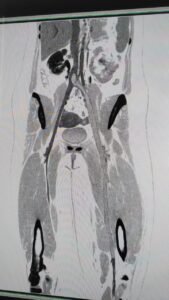

ಅವರನ್ನು ಪರೀಕ್ಷೆ ಮಾಡಿದ ಬಳಿಕ ಪಡೆದ ಬಳಿಕ ಎಡ ಗಾಲಿನ ಕಾಲಿನಲ್ಲಿ ರಕ್ತ ಗೆಪ್ಪುಗಟ್ಟಿದ್ದು, ಹೃದಯದಿಂದ ಶ್ವಾಸಕೋಶದ ಪಲ್ಮನರಿವರೆಗೆ ಬ್ಲಾಕೇಜ್ ಆಗಿರೋದು ತಿಳಿದುಬಂದಿದೆ. ಅಲ್ಲದೇ ಎಡ ಗಾಲಿನ ರಕ್ತನಾಳ ಸಂಪೂರ್ಣ ಹೆಪ್ಪುಗಟ್ಟಿದ್ದು, ರಕ್ತ ಸಂಚಲನಕ್ಕೆ ಜಾಗ ಇಲ್ಲದೇ ಜಾಮ್ ಆಗಿತ್ತು . ಹಾಗಾಗೀ ಶ್ವಾಸಕೋಶದಲ್ಲಿ ರಕ್ತ ಸಂಚಲನ ಫುಲ್ ಬಂದ್ ಆಗಿತ್ತು. ರಕ್ತ ಕರಗಿಸೋಕೆ ಇಂಜೆಕ್ಚನ್ ನೀಡಿದ್ರೂ ರೋಗಿಯಲ್ಲಿ ಯಾವುದೇ ಬದಲಾವಣೆ ಕಂಡು ಬಂದಿಲ್ಲ. ಬಳಿಕ ಅವರಿಗೆಸಿಟಿ ವಿನೋಗ್ರಾಮ್ ನಡೆಸಲಾಯ್ತು, ಅದರಲ್ಲಿ ಅವರಿಗೆ ಥ್ರಂಬೋಸಿಸ್ ಖಾಯಿಲೆ ಇರೋದು ತಿಳಿದು ಬಂದಿದೆ. ಅದಕ್ಕಾಗಿ ಪಲ್ಮನರಿ ಎಂಬೋಲೆಕ್ಟಮಿ ಹಾಗೂ ವೀಸನ್ ಥ್ರಂಬೆಕ್ಟಮಿ ಅಪರೇಷನ್ ಮಾಡಿಸುವ ಅಗತ್ಯತೆಯನ್ನು ಹೃದಯ ತಜ್ಞ ಡಾ ರಾಮ್ ನರೇಶ್ ಸೌದ್ರಿ ರೋಗಿಗೆ ತಿಳಿಸಿದ್ದಾರೆ.